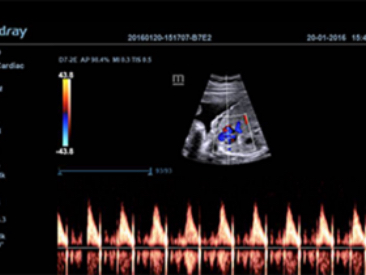

Images cliniques